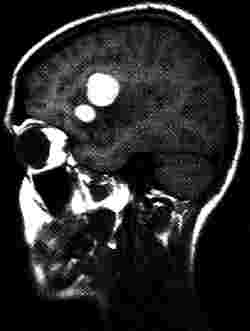

Aneurysma im Bifurkationbereich der linken Arteria cerebri media

Aus: Lissner, J., Seiderer, M. (1990)